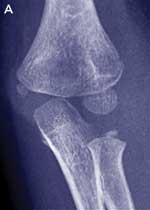

Case study — a 4-year-old girl with a painful left elbow after a fall

The parents of a 4-year-old girl bring their daughter to you after she has fallen about 1 metre from climbing equipment onto her outstretched arm. The girl is complaining of pain in her left elbow. She is unable to straighten her arm without pain and can only flex to 110°. The elbow looks swollen, mainly on the medial aspect. She has diffuse tenderness around the elbow and is unable to supinate or pronate her arm. There is no neurovascular compromise. Management

Lateral condyle fractures are inherently unstable and take a longer time to heal than supracondylar fractures. They should be managed by internal fixation in most cases. This case illustrates that it may be difficult to diagnose these fractures and that close follow-up is needed to prevent complications. |